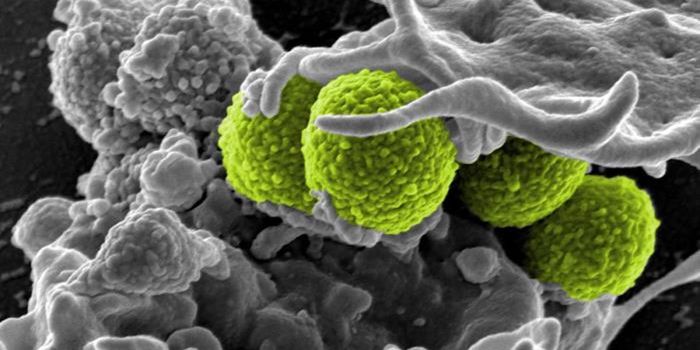

SEP 17, 2021Cell & Molecular BiologyMRSA (methicillin-resistant Staphylococcus aureus) is a well known superbug, a pathogenic microbe that can cause serious ...